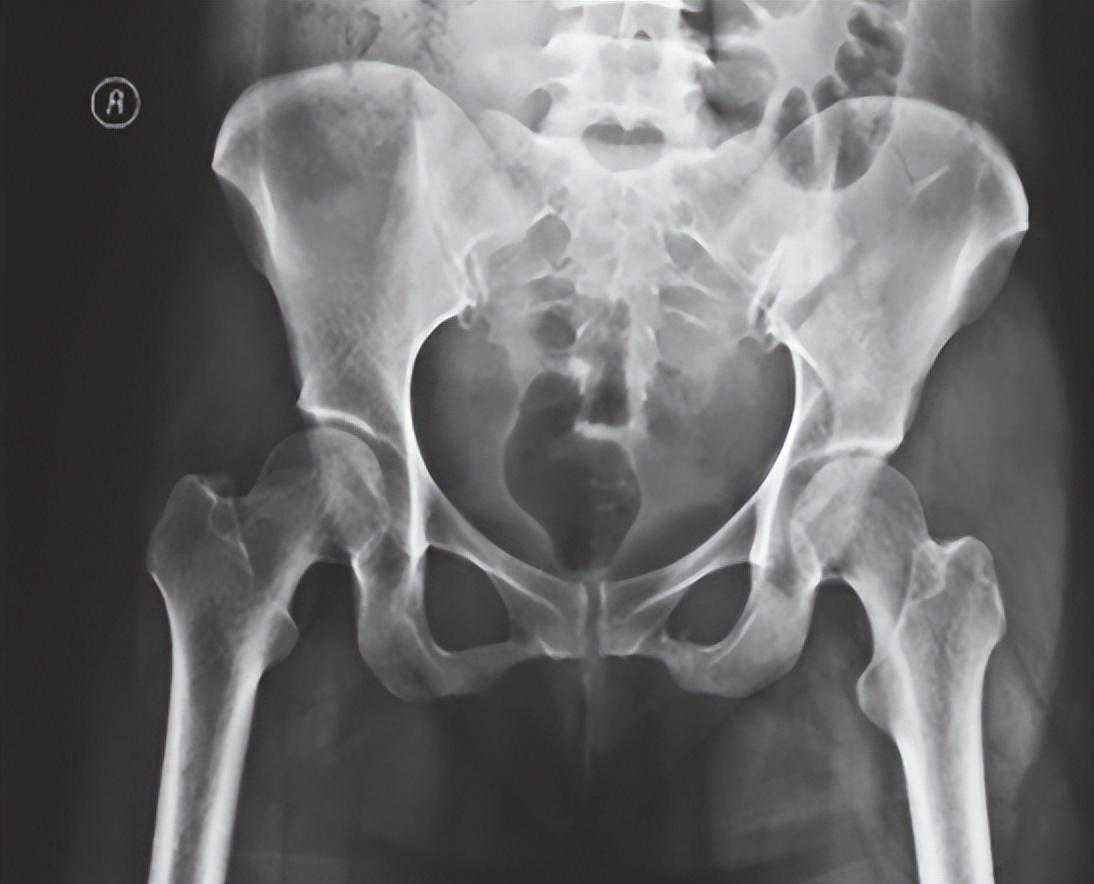

1、骨盆前后位X线检查(骨盆正位X线检查):

最为常用,患者仰卧,射线呈前后方向垂直投射,骨盆入口边缘与躯干纵轴呈45°~60°夹角。该位像基本能了解骨盆前后环骨折及骶髂关节骨折脱位情况。可用于鉴别骶骨、骨盆髋臼、近端股骨等部位骨折(图1)。

图1骨盆前后位X线片可见左侧骶髂关节骶骨及髂骨面局部骨质断裂,关节间隙增宽,左侧耻上、下支骨折,累及耻骨联合左侧缘。